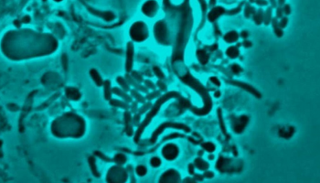

فيروس "شيكونجونيا" يصيب الخلايا البشرية ومن أعراضه حمى أولية مفاجئة من يومين إلى 7 أيام وقد يسبب آلاما تدوم أسابيع حتى سنوات